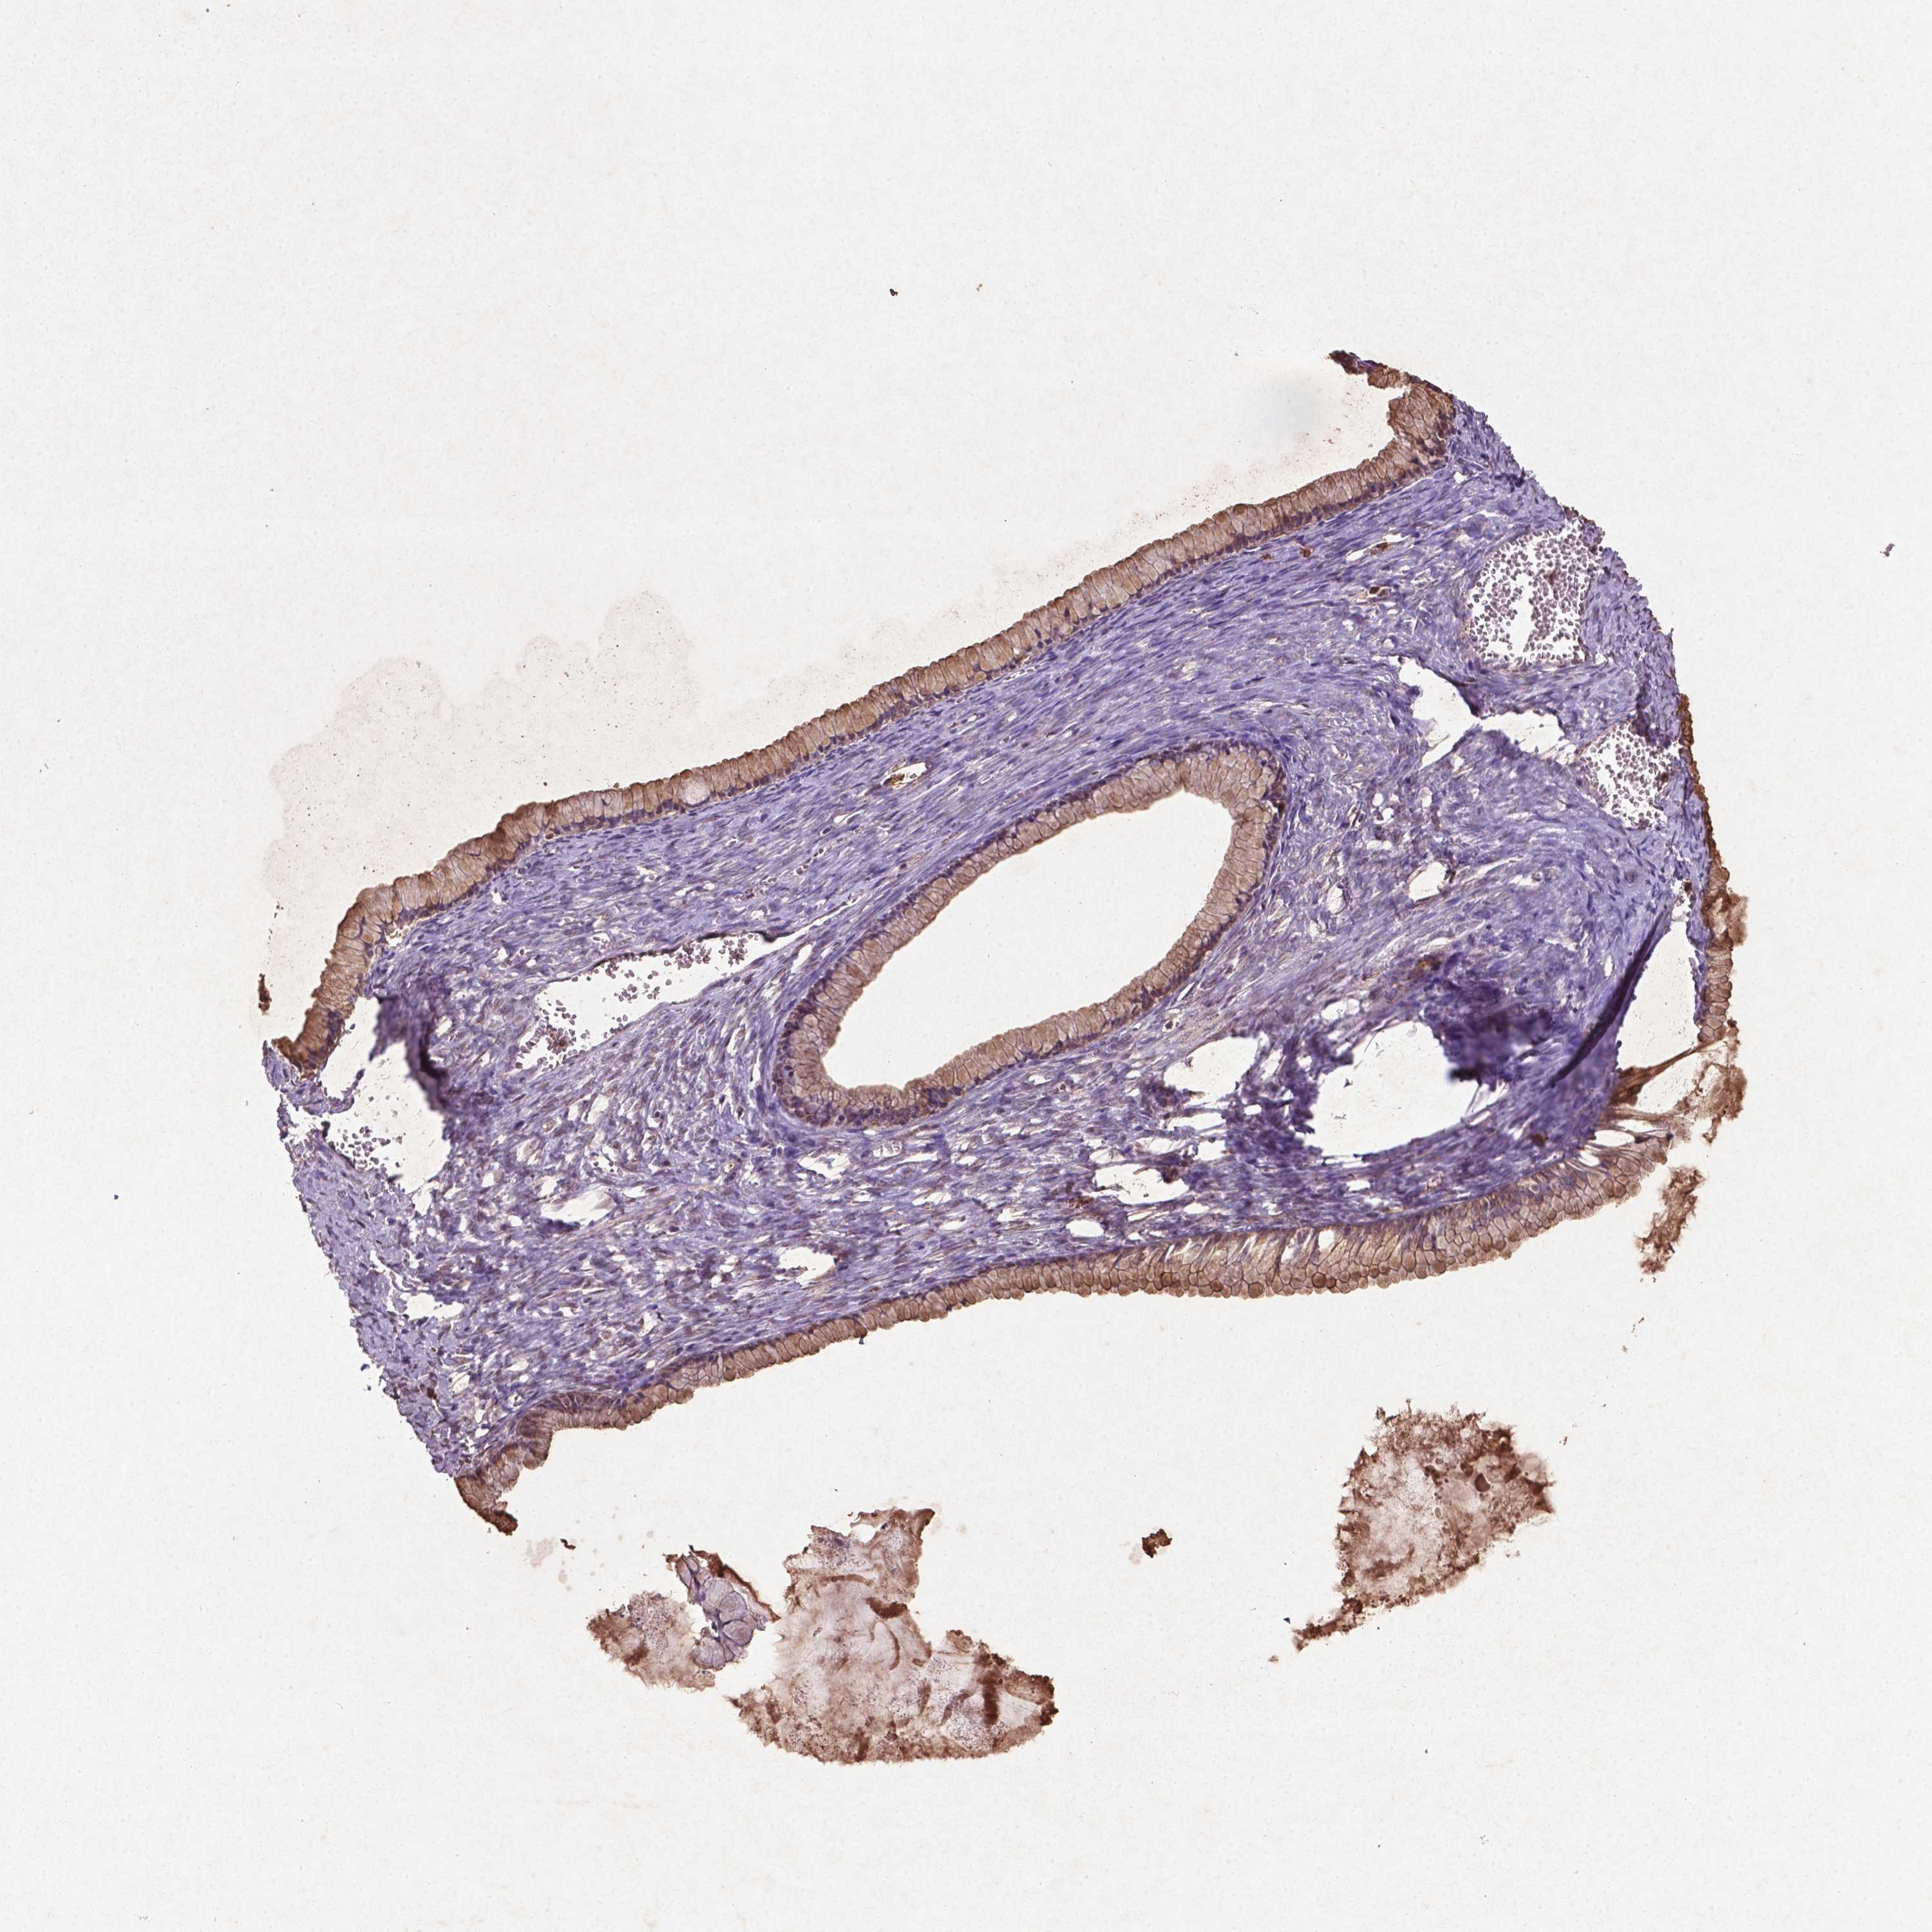

OVARIAN CANCER - Protein expressioni

A mouse-over function shows sample information and annotation data. Click on an image to view it in a full screen mode. Samples can be filtered based on level of antibody staining by selecting one or several of the following categories: high, medium, low and not detected. The assay and annotation is described here.

Note that samples used for immunohistochemistry by the Human Protein Atlas do not correspond to samples in the TCGA dataset.

Antibody stainingi

Antibody staining in the annotated cell types in the current human tissue is reported as not detected, low, medium, or high, based on conventional immunohistochemistry profiling in selected tissues. This score is based on the combination of the staining intensity and fraction of stained cells.

Each image is clickable and will lead to virtual microscopy that enables deeper exploration of all samples and also displays staining intensity scores, fraction scores and subcellular localization as well as patient and tissue information for each sample.

Cystadenocarcinoma, serous, NOS

Cystadenocarcinoma, mucinous, NOS

Carcinoma, endometroid